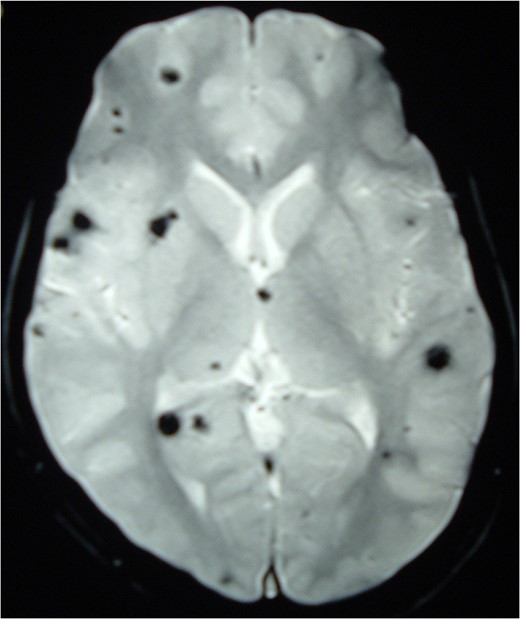

Magnetic resonance imaging (MRI) of the brain and spine showed multiple hypointense lesions in the brain and one mixed intense lesion with a hyperintense rim intrinsic to the spinal cord at the level of C5 with evidence of fresh bleeding (Figs 1–3). He was diagnosed with multiple cerebral cavernomas and an acutely bleeding spinal cavernoma. The patient was scheduled for a laminectomy and total excision of the spinal cavernoma and to control further hemorrhage. Bone removal was limited to the site of malformation. The lesion was identified by the bluish discoloration on the dorsal surface of the spinal cord (Fig. 4). A myelotomy was made over the discoloration and the lesion was excised inside out. Intraoperative evoked potential monitoring was not used for our procedure due to lack of availability.

MRI Brain (GRE T2WI) showing multiple hypointense lesions diagnosed as cerebral cavernomas.

Intramedullary spinal cavernomas may be associated with multiple concurrent occult cerebral cavernomas as seen in our case. This makes MRI of the complete neuraxis a crucial next step [1, 4, 5]. Familial CM syndrome should be suspected for any case with multiple cerebral cavernomas [4]. MRI remains the gold standard for diagnosing both cerebral and intramedullary cavernomas. They appear as mixed signal intensity lesions in on T1 and T2-weighted images surrounded by a low-signal intensity zone (due to hemosiderin deposits) best seen on T2-weighted images [4, 5, 8].